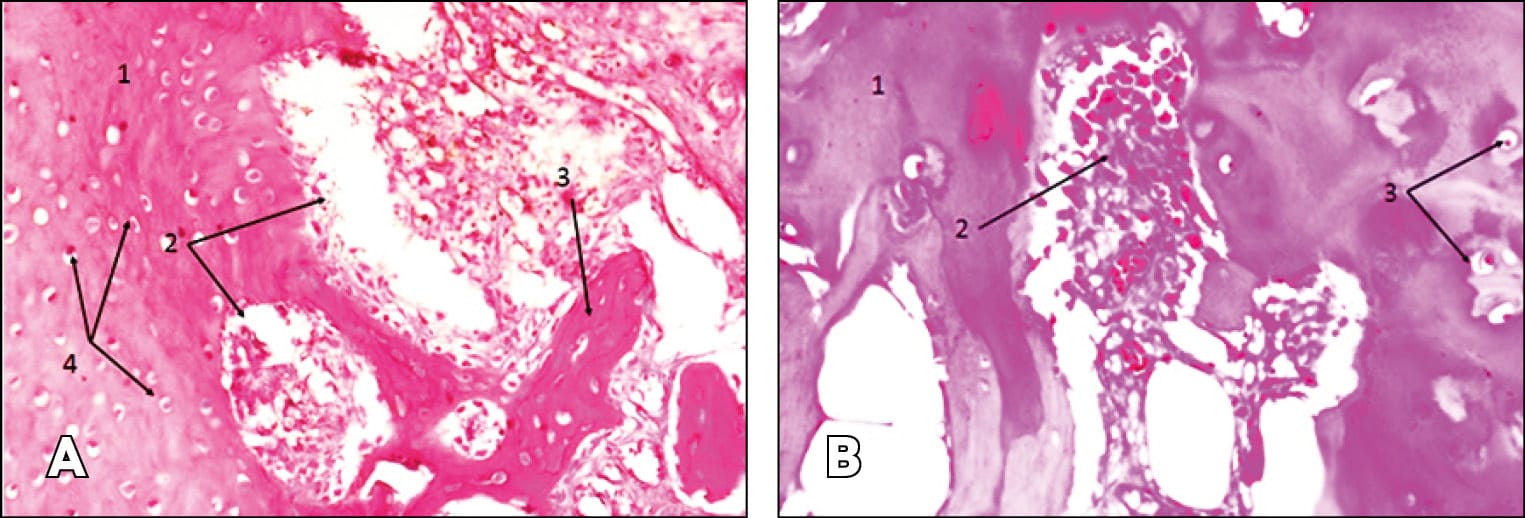

Destructive changes are more noticeable in osteoarthrosis. In the case of SOA, cartilage tissue samples show proliferation with foci of destruction (Figure 6 A). The same foci of destruction are evident against the background of normal cartilage tissue (Figure 7 B). In bone tissue samples, sequestra surrounded by a large number of neutrophils and leukocytes are noted, along with lymphoplasmacytic infiltration (Figure 5 A).

In SOA, we observe vessel wall destruction, lymphoplasmacytic infiltration, vascular fibrosclerotic changes, signs of hyperemia (numerous capillaries), fibrosis of adipose tissue, formation of bone sequestra, and multiple neutrophils and leukocytes (Figures 4 B, 5 A).

In the case of SSOA, destructive foci are observed in the cartilage tissue samples, primarily with plasma cells that, in some areas, penetrate into the normal cartilage tissue (Figure 6 B). SSOA is accompanied by the formation of bone sequestra surrounded by a large number of neutrophils and leukocytes. Lymphoplasmacytic infiltration is present, and dilated sinus-like vessels filled with blood are visible (Figire 7 A).

The histological analysis data we obtained somewhat confirm this. Cellular infiltration was detected in all groups. However, in patients with SSA and SSOA, it was relatively moderate. Similar results have been published in the literature on experimental arthritis [38] Kamarudin, T.A.; Othman, F.; Mohd Ramli, E.S.; Md Isa, N.; Srijit, D. Protective effect of curcumin on experimentally induced arthritic rats: detailed histopathological study of the joints and white blood cell count. EXCLI Journal 2012;11:226-236 – ISSN 1611-2156.. Neutrophils, leukocytes, lymphocytes, lymphoplasmacytic infiltration, paralytic dilated sinus-like capillaries, intravascular stasis, vascular fullness, and fibrosclerotic changes were found in all patients, but no significant differences between groups were found. The morphology of SA, regardless of etiology, is usually similar and is usually accompanied by significant destruction of all joint components. In the background of steroid administration, this process becomes more acute, especially noticeable when examining cartilage tissue. For example, in the case of SOA, cartilage specimens show proliferation with foci of destruction. In the case of SSOA, destructive foci, mainly with plasma cells, penetrated normal cartilage tissue in some areas (Figure 6B). SSOA is characterized by the formation of bone sequester, surrounded by a large number of neutrophils and leukocytes.

Thus, in steroid arthritis, the thickness of cartilage tissue was less compared to the other group, and the depth of the destruction site was greater. Getmanets, A.V. (2012) observed similar results in creating experimental arthritis in animals [26] Getmanets, A.V. Evaluation of the influence of experimental arthritis of the knee joint on the structure of the proximal epiphyseal cartilage of the tibia. Ukrainian morphological almanac - 2012. - Volume 10, No. 3. - P.149-152.. Comparing the data of morphological and microbiological studies, it can be suggested that the introduction of steroid preparations into the joint possibly initially causes changes in joint tissues that lead to cell necrosis of soft tissues with the development of an aseptic inflammatory process. This may occur as a result of disrupting POL processes, which intensify with the introduction of steroid preparations [39] T Ichiseki, A Kaneuji, S Katsuda, Y Ueda, T Sugimori, T Matsumoto. DNA oxidation injury in bone early after steroid administration is involved in the pathogenesis of steroid-induced osteonecrosis Rheumatology (Oxford) 2005 Apr;44(4):456-60. doi: 10.1093/rheumatology/keh518. Epub 2004 Dec 14.. With repeated intra-articular steroid injections, the percentage of such necrosis can significantly increase [40] Ozan Beytemur, Mustafa Fatih Dasci,Asiye Gök Yurttaş, Busra Yaprak Bayrak, and Ender Alagöz. The protective role of vitamins C and E in steroid-induced femoral head osteonecrosis: An experimental study in rats. Jt Dis Relat Surg. 2024 Jan; 35(1): 72–84. Published online 2023 Nov 2. doi: 10.52312/jdrs.2023.1405. M Suntiparpluachac et al. (2016) suggest that corticosteroids increase oxidative stress and alter the expression of genes such as cyclin-dependent kinase inhibitor 1A, growth differentiation factor 15, and c-Fos, which are involved in cell death and chondrotoxicity [41] M Suntiparpluachac , N Tammachote, R Tammachote. Triamcinolone acetonide reduces viability, induces oxidative stress, and alters gene expressions of human chondrocytes. Eur Rev Med Pharmacol Sci. 2016 Dec;20(23):4985-4992.. Pattaranatcha Charnwichai et al. (2023) also show that TA induces chondrotoxicity by enhancing oxidative stress and altering gene expression involved in cell death. The authors studied and compared histological analyses of materials obtained from patients undergoing knee joint arthroplasty. They showed that in patients who received intra-articular corticosteroid injections six months before the operation, a decrease in the thickness of articular cartilage was noted. The same decrease in articular cartilage thickness was noted in our study [42] Pattaranatcha Charnwichai, Rachaneekorn Tammachote, Nattapol Tammachote, Thiamjit Chaichana, and Nakarin Kitkumthorn. Histological features of knee osteoarthritis treated with triamcinolone acetonide and hyaluronic acid. Biomed Rep. 2023 Jun; 18(6): 40. Published online 2023 May 8. doi: 10.3892/br.2023.1623. Indirectly, the high number of negative microbiological analyses in patients in the acute phase of SSA - 66.7%, speaks to the primacy of aseptic cell necrosis.